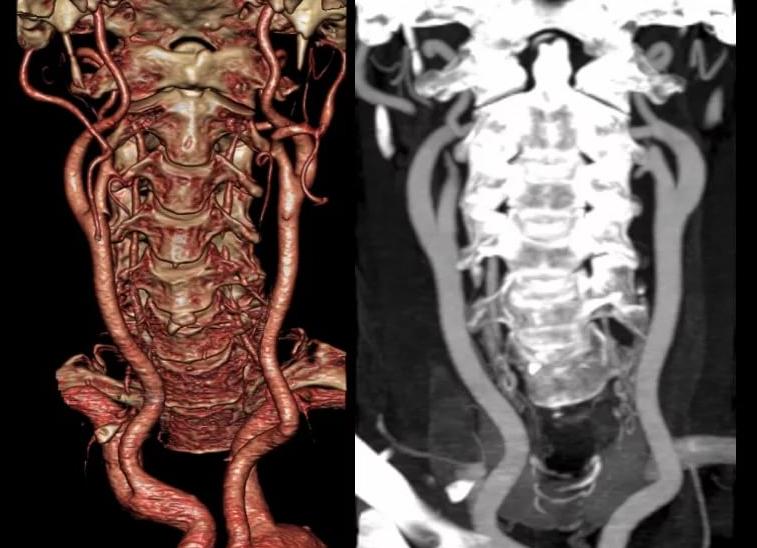

МРТ исследование является одним из самых современных методов изучения организма человека, которое широко используется при диагностике разных патологических состояний головного мозга. Благодаря ей можно увидеть любой орган послойно, а также очень точно оценить состояния структуры мягких тканей. Этот вид томографии является безопасным, качественным и высокоинформативным диагностическим исследованием.